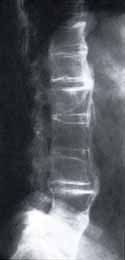

Figura 5. Radiografía Simple de Columna Lumbar. Proyección Lateral: Rectificación de la lordosis lumbar. Cuadratura de los cuerpos vertebrales. Disminución de los espacios intervertebrales. Calcificación del ligamento longitudinal anterior que se extiende a lo largo de toda la columna lumbar. Anquilosis entre L4 y L5.

-A. Además de confirmar los hallazgos anteriormente descritos en la figura 5, se visualiza un aumento heterogéneo en la intensidad de la señal de los discos intervertebrales y alteración de la intensidad de la señal de las áreas subcondrales adyacentes notándose lesiones extensas comprometiendo la unión discovertebral periférica y central (lesión tipo III). Canal estrecho a nivel del espacio L3, L4.

-B. Calcificación del ligamento longitudinal anterior. Engrosamiento del ligamento longitudinal posterior. Sindesmofitos marginales posteriores entre L1, L2 y L2 , L3. Erosiones discales con herniación del núcleo pulposo hacia las regiones subcondrales.